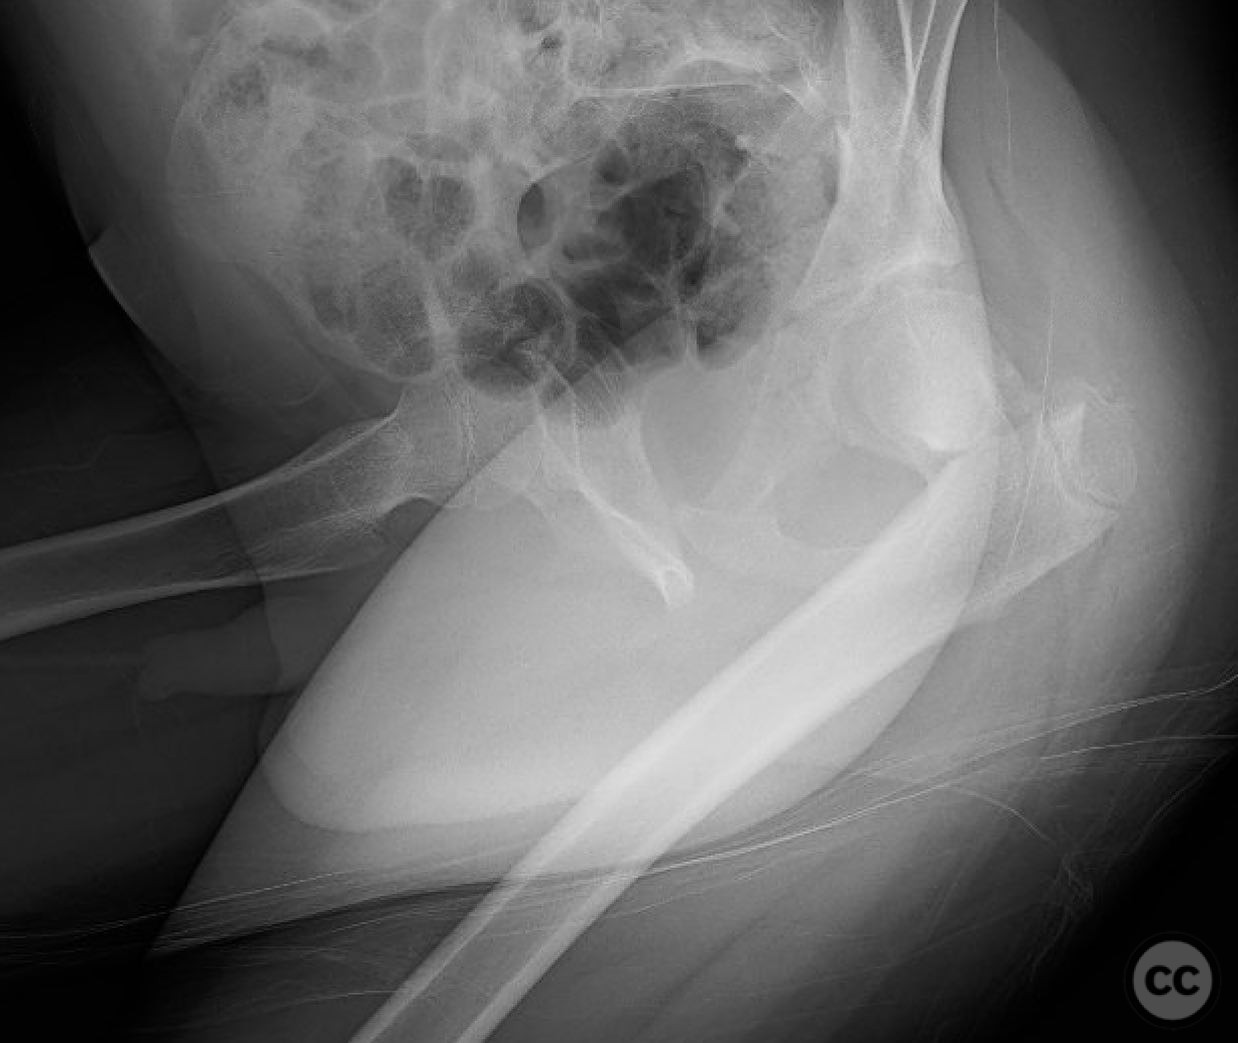

Clinical and radiological findings:  An 8-year-old boy fell approximately 15 feet from a treehouse, sustaining a displaced femoral neck fracture. There were no associated injuries to the head, spine, chest, or abdomen. The initial radiological assessment confirmed a displaced fracture of the femoral neck. Neurovascular examination was unremarkable.

Preoperative Plan

Planning remarks:  The preoperative plan involved achieving a direct anatomic reduction and stable fixation of the femoral neck fracture. The surgical approach considered was a modified Smith-Petersen approach for optimal visualization and reduction, followed by a separate lateral approach for implant application.